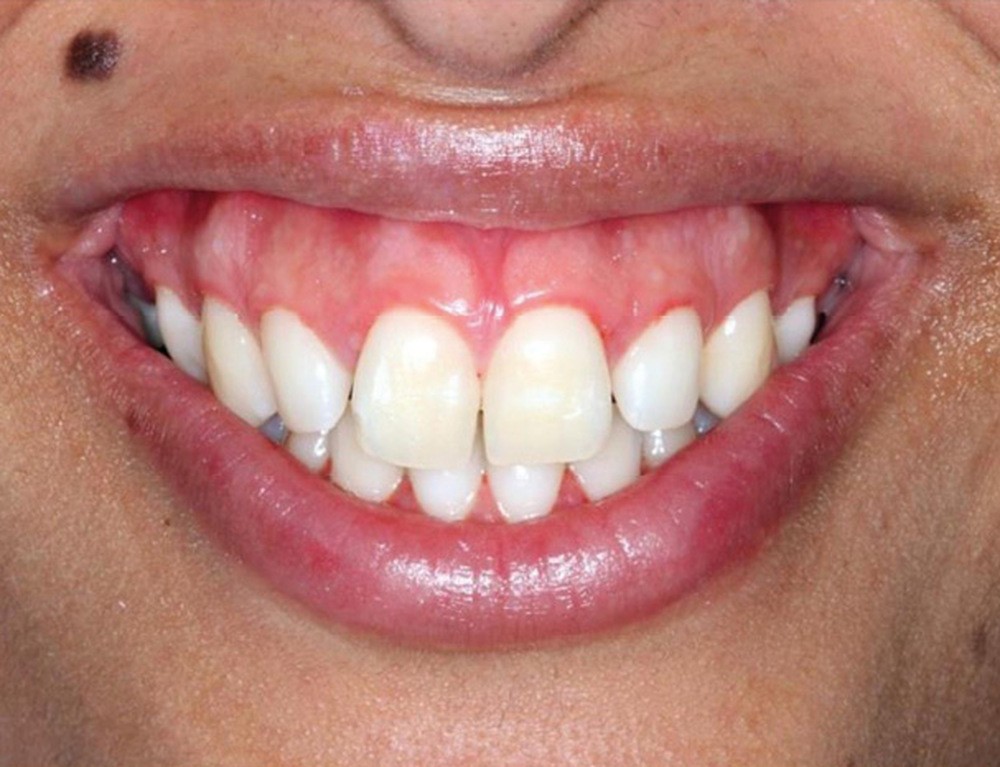

C’est à ces questions que nous permettront de répondre les deux premiers conférenciers, parodontologistes : le Dr Béatrice Straub nous présentera le renfort parodontal minéralisé, technique qu’elle a développée et pratique depuis de nombreuses années, pour éviter les préjudices des mouvements orthodontiques à risque, notamment lors des décompensations préchirurgicales (fig. 1a-d) ; le Pr Anton Sculean abordera le thème des greffes, avec leurs indications, les différentes techniques à privilégier et illustrera ses propos par de nombreux cas cliniques aux résultats esthétiques impressionnants.

À côté de la coopération moindre qu’ils exigent, les ancrages squelettiques présentent également l’avantage de répondre à des indications très variées : correction des sourires gingivaux (Dr Skander Ellouze, fig. 3a-c), distalisation ou mésialisation molaire, supports pour les masques faciaux, mini transpalatin sur vis après expansion, ressorts de rétraction pour mettre en place les canines incluses sans léser les racines des dents adjacentes [3] (Dr Stéphane Renger, fig. 4) ou appareils d’expansion maxillaire (Dr Hans Winsauer, Dr Guido Sampersmans, fig. 5a-c)…